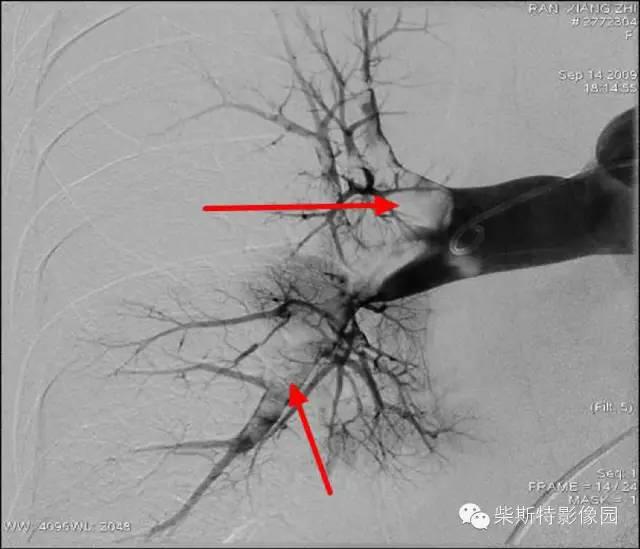

第一大名捕:肺动脉造影

红色箭头所指处即为栓子导致的充盈缺损。尽管肺动脉造影目前已经被肺动脉CTA所替代,但是其“老大”的地位还是无法撼动!

“老大”的绝招是其不仅可以提供整体的肺血管的解剖学资料,而且可以提供血流动力学参数,即可以用于诊断也可以用于治疗,如急性肺栓塞的导管内局部溶栓、捣栓、碎栓、抽栓,先天性肺动脉狭窄的球囊扩张、支架植入、肺动静脉瘘的栓塞治疗等。